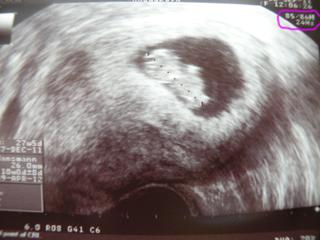

uz se mi to konecne krati, uz jsme za pulkou v cekani na sono naseho pipiska.))uz jen 12dni a vidime ho🙂)

@strihalka so mnou bol manžel na UTZ teraz v pondelok, to som bola 10+4 😉 drobček sa mu krásne predviedol, pekne kopkal, hýbal ručičkami, bolo to fakt úúúúúúúúúúžasnéééééééééééé

@sunday1 ja som to skúšala. na ľavej strane nad lonovou kosťou a tlačiť som musela dosť, aby som to zachytila. uvidím o 2tt, keď budem v 12tt a budú mi robiť už aj sono, ktoré určí TP poriadne 🙂 teraz mi na sone nepustili srdiečko, tak som nepočula. ale tak snáď mu to tam pomeralo 😉